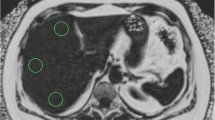

The entire hepatic assessment was performed by qualified professionals of the CUN under fasting conditions. The diagnosis of NAFLD was determined by ultrasonography (Siemens ACUSON S2000 and S3000), as described elsewhere [44]. The participants were classified into two groups: 0 (controls) and ≥ 1 (NAFLD). MRI (Siemens Aera 1.5T) determined liver fat content by the Dixon technique [6]. Aspartate aminotransferase (AST), alanine aminotransferase (ALT), and gamma-glutamyl transferase (GGT) were quantified on an autoanalyzer with specific commercial kits and following the instructions of the company (Cobas 8000, Roche Diagnostics, Switzerland). M30 and M65, which are considered hepatic fibrosis markers [36], were quantified with an enzyme-linked immunosorbent assay (ELISA) method using commercial kits (PEVIVA, Bromma, Sweden) according to the manufacturer’s instructions. The fatty liver index (FLI) was computed using a previously described formula [3], that considers serum triglycerides, BMI, waist circumference, and GGT concentrations to determine the probability of suffering NAFLD.

Metabolomic fingerprint of controls and NAFLD subjects. A. Principal component analysis (PCA) in positive polarity of controls and NAFLD subjects. B. Volcano plot in positive polarity of controls and NAFLD subjects. C. Principal component analysis (PCA) in negative polarity of controls and NAFLD subjects. D. Volcano plot in negative polarity of controls and NAFLD subjects